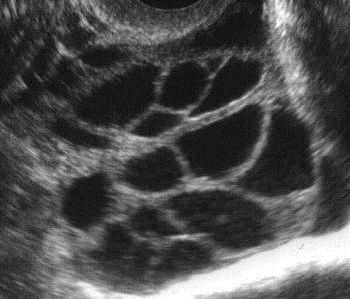

• pólen é rico em hormônio do prolongamento que, segundo pesquisas, aumenta a resposta dos ovários às gonadotropinas (hormônios secretados pela hipófise).Este hormônio auxilia a produção de estrogênio e tem efeito positivo em casos de pistilo policístico, anovulatório e alguns tipos de infertilidade.